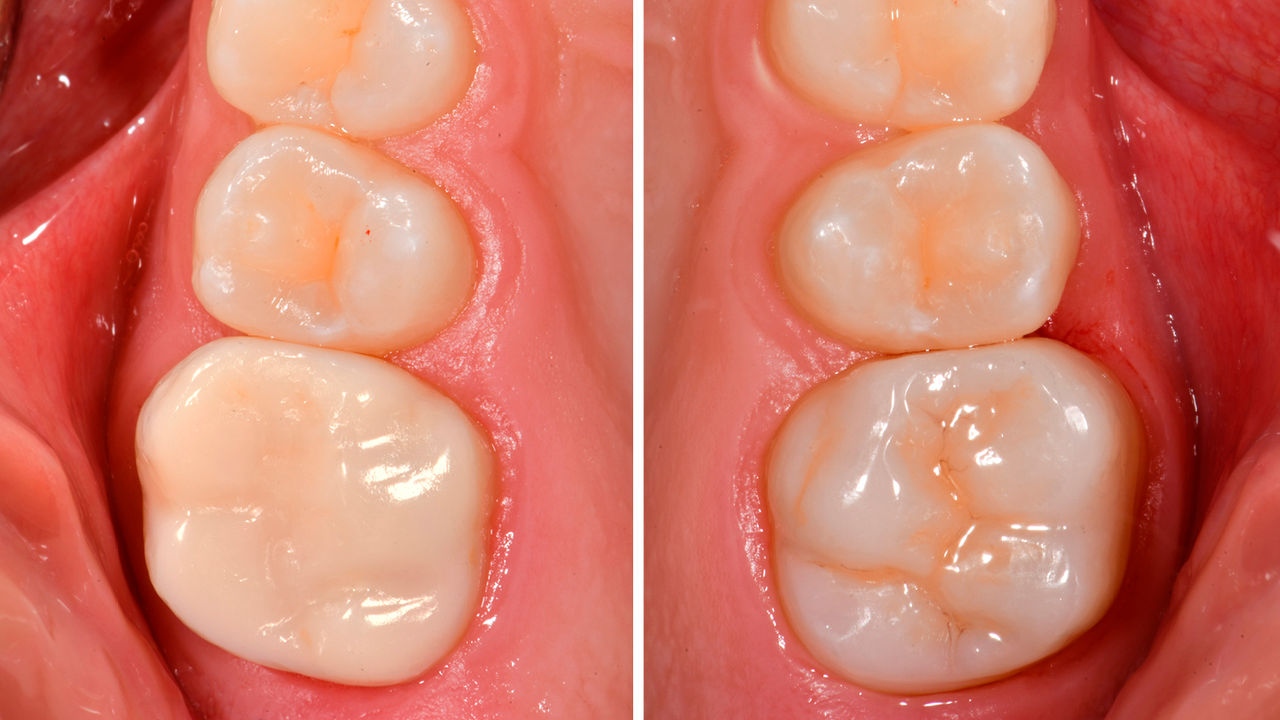

Klinikte alt ikinci molar restorasyonu

Kısmi CEREC Tessera kuronu

Bukkal yüzeyde kapsamlı bir Sınıf I kompozit restorasyonun yanı sıra çatlaklarla birlikte, hassas alt ikinci molar. Minimal invazif konsepte göre, tek bir ziyarette CEREC Tessera kullanılarak CAD/CAM kısmi kuron planlandı, imal edildi ve bağlandı.

Önce: Değiştirme gerektiren başarısız amalgam restorasyonu. Hasta hassasiyetten şikayet ediyor ve dişte birden fazla çatlak bulunuyor.

Sonra: Klinikte, CEREC Tessera Gelişmiş Lityum-Disilikat cam seramikten imal edilmiş CAD/CAM kısmi kuron restorasyonu.

Dr. Carlos Eduardo Sabrosa